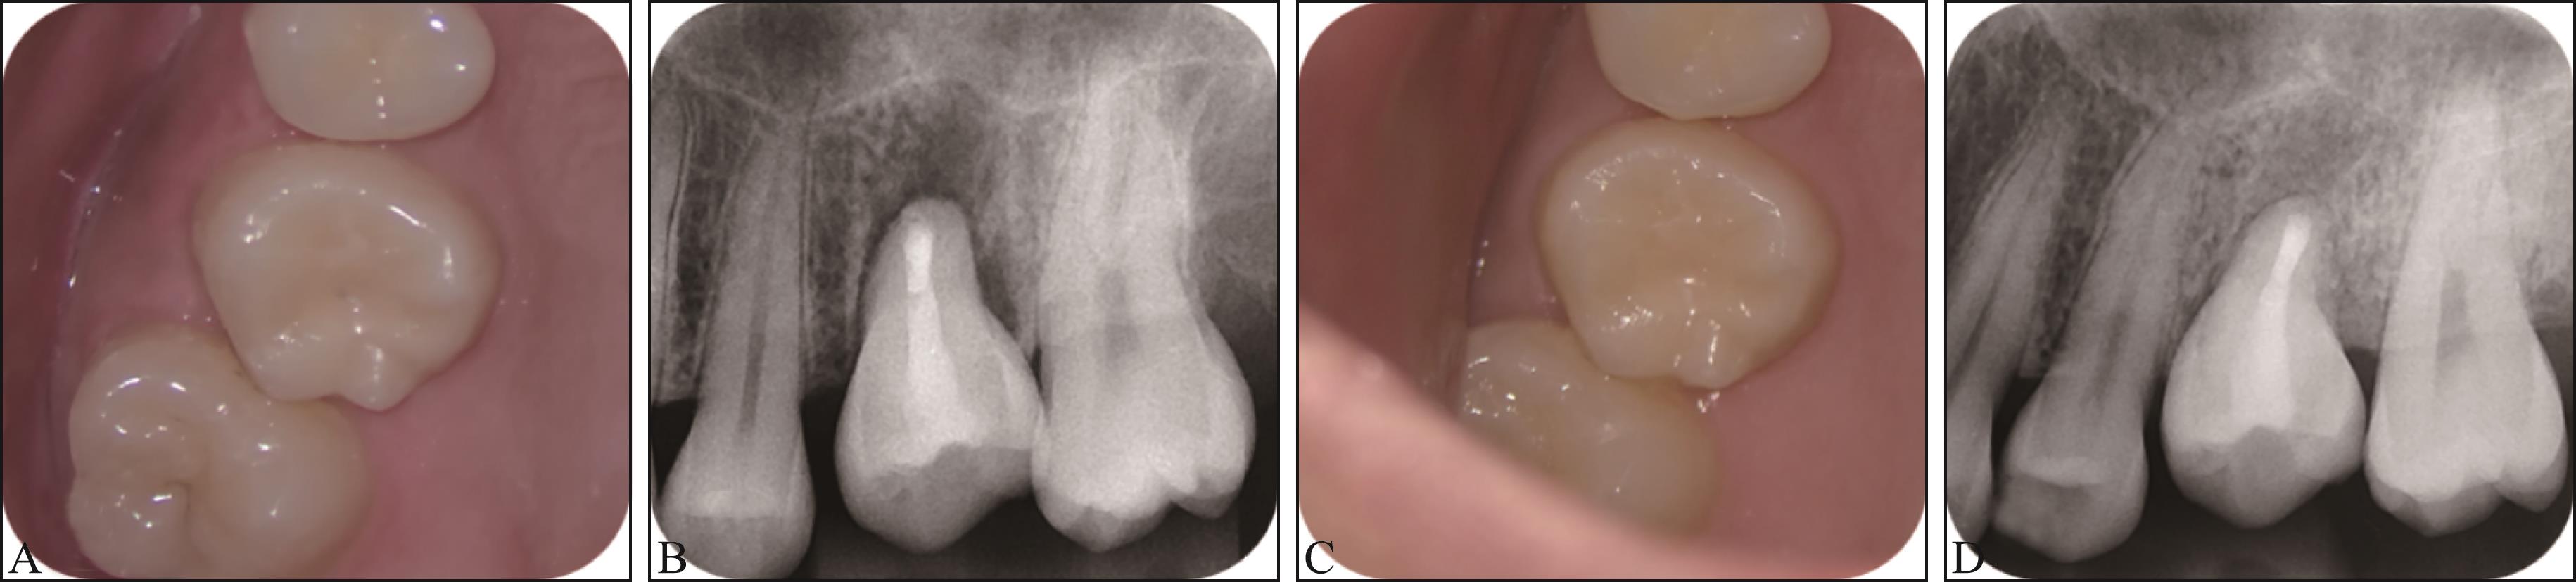

Keranmu D, Ainiwaer A, Nuermuhanmode N, et al. Application of concentrated growth factor to autotransplantation with inflammation in recipient area[J]. BMC Oral Health, 2021, 21(1): 556.

|